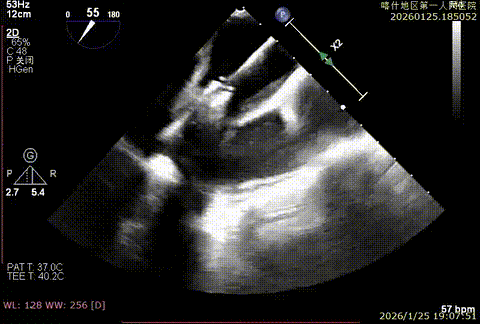

该例患者为DMR,1,2,3区均见脱垂,主要脱垂位于1区及外交界后叶脱垂,病变解剖结构亦相对复杂。术前制定手术策略:使用3把XTR解决患者瓣叶脱垂与二尖瓣反流。术中首先进行房间隔穿刺,最终穿刺高度4.5cm。穿刺成功后将SGC和XTR-CDS依次送入左心房,通过操控“M”旋钮调节SGC,使二尖瓣夹避开华法林脊并成功定位于2区正上方。在2区进行弹道测试成功后,进行Orientation调整。最终在1区将二尖瓣夹送入左心室,成功捕捞和夹持瓣叶后缓慢关紧夹。第二枚XTR植入2区,采用双拉链技术,从两个夹子中间植入第三枚夹子,固定脱垂区域降低反流。TEE检查见二尖瓣反流程度降低至少量,二尖瓣双孔组织桥稳定,肺静脉逆流改善明显,手术安全结束。

bicomm切面-大脱垂

X-plan 1区后叶脱垂

3D enface脱垂情况

X-plan 反流情况